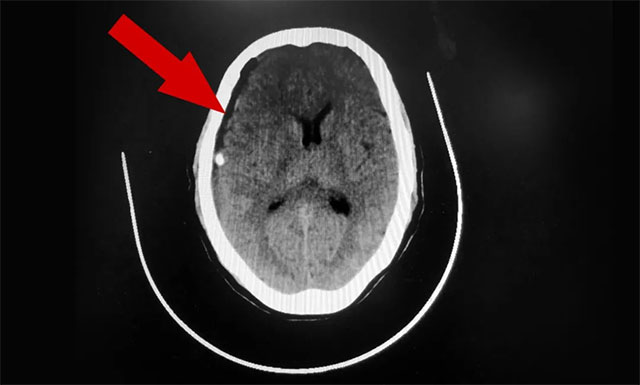

在排除手術(shù)禁忌,明確告知家屬手術(shù)風(fēng)險(xiǎn)并獲得簽字同意后,侯增欣主任為患者開展了顱骨鉆孔引流手術(shù)。手術(shù)進(jìn)展順利,術(shù)后患者未出現(xiàn)明顯并發(fā)癥,意識(shí)正逐步恢復(fù)清醒。

▲ 術(shù)后,患者硬膜下血腫已被引流清除